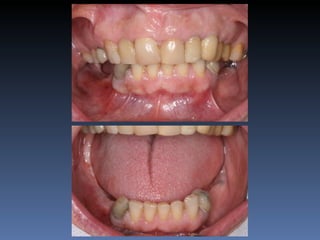

BOX 5

Maria Gomes Moraes

Idade – 53 anos

Sexo – Feminino

Raça – Caucasiana

ASA – II

Data- 23-04-2012

Diagnóstico: Atrofia severa

da pré-maxila.

Plano de tratamento: Aumento de volume horizontal

com blocos ósseos autógenos “onlay” provenientes do

Ramus da Mandíbula.